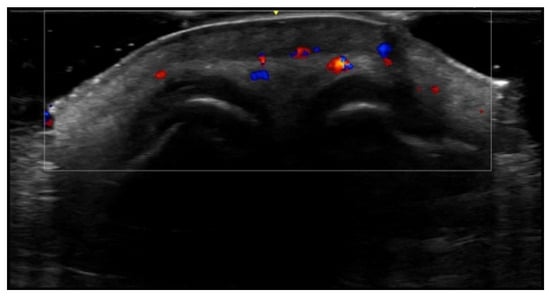

- Cataldo-Cerda, K.; Wortsman, X. Dissecting Cellulitis of the Scalp Early Diagnosed by Color Doppler Ultrasound. Int. J. Trichology 2017, 9, 147–148. [Google Scholar] [CrossRef]